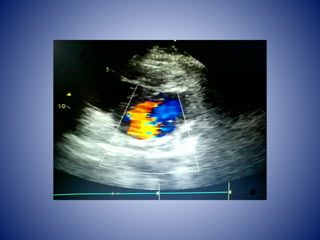

• Trans Esophageal Echocardiography done on

1ST Feb showed Mitral valve Vegetation

measuring 1.2 x 0.7 cm attached to AML, Flail

AML, non coapting leaflets with severe MR,

Aortic vlve – tri leaflets , No AR, pulmonary

valve normal, no PR, Tricuspid valve- mild TR,

Left Atrium mildly dilated , no LA appendage

clot.

• USG Abdomenshowed mild hepatomegaly, mild bilateral pleural effusion , dilated IVC and Hepatic veins. Patient improved symptomatically with diuresis. • Trans Esophageal Echocardiography done on 1ST Feb showed Mitral valve Vegetation measuring 1.2 x 0.7 cm attached to AML, Flail AML, non coapting leaflets with severe MR, Aortic vlve – tri leaflets , No AR, pulmonary valve normal, no PR, Tricuspid valve- mild TR, Left Atrium mildly dilated , no LA appendage clot.